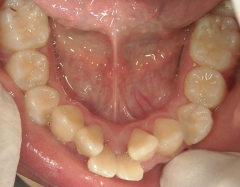

矯正歯科 治療前 左右上下4番  計4本抜歯

矯正_灰色.pngno.18_2196_治療前_上.jpg矯正_灰色.png

矯正_灰色.pngno.18_2196_治療前_下.jpg矯正_灰色.png